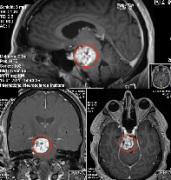

【手术报告】少见滑车神经鞘瘤误诊为中脑脑膜瘤,二次手术成功全切

摘要:被误诊并手术失败的少见滑车神经鞘瘤,德国INI手术详细治疗 L先生,30+岁,因为复视、左侧面部感觉麻木伴有吞咽困难,就诊当地医院,进行了MRI检查显示右侧中脑病变,怀疑...